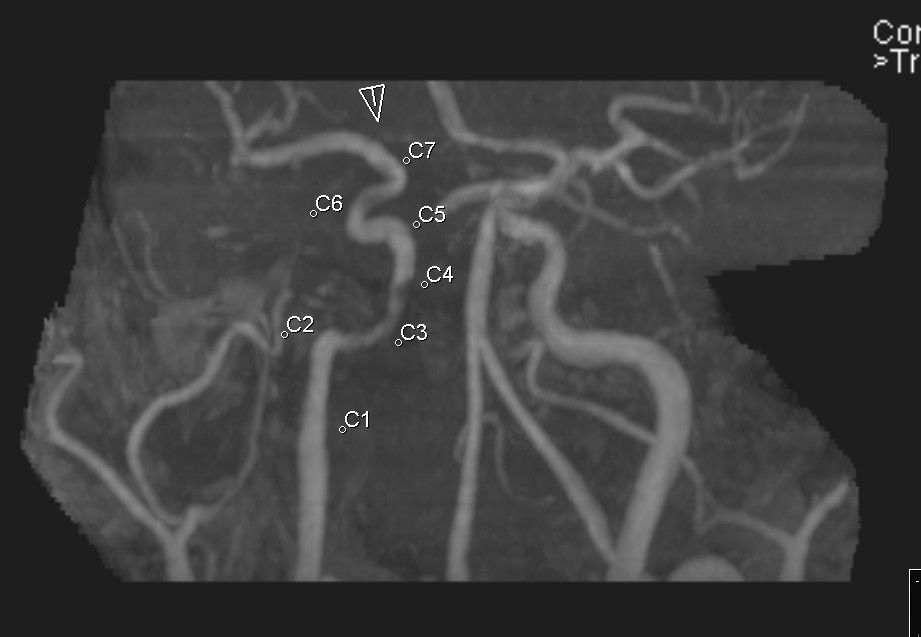

Сегменты сонной артерии кт

Сегменты сонной артерии кт 83 фото